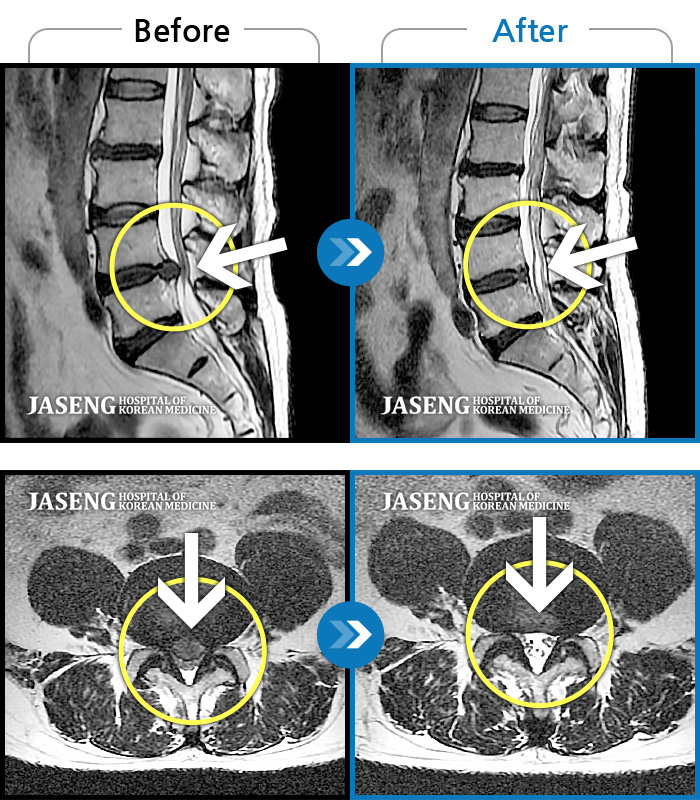

휴직중 허리디스크로 걷지도 못하고 정형외과에서 전부 수술을 권유하는 저에게 비수술로 희망을 주셨어요~^^

지금도 통증이 있으면 통원을 가는데 갈때마다 한결 같으신 원장님 추천합니다~^^

MRI사진에서 좋아지고 있다는 말씀에 넘 기뻤습니다^_^